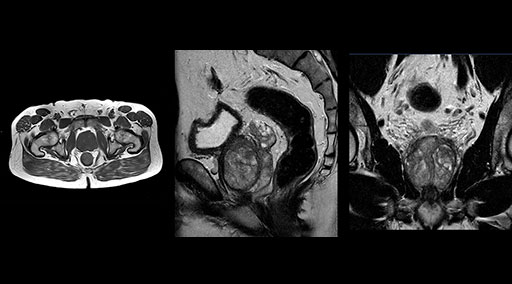

“Without using an endorectal coil we do our prostate MR at 0.5 mm resolution, following the European society of urology protocol [1]. For certain joints we use a virtual arthroscopy protocol with 1 mm pixel size and 2 mm slice thickness. Ingenia really excels in our neurography, brachial plexus and prostate scans. Our neurologists insist on using our 3.0T for those,” Dr. Kaakaji adds.

“Our DMG Lisle location includes a cancer center, so soft tissue neck scans, brachial plexus scans, and prostate scans are common. For these exams, mDIXON TSE provides excellent images with and without fat suppression all while helping us reduce repeats and work more efficiently,” Mr. Duffy says.